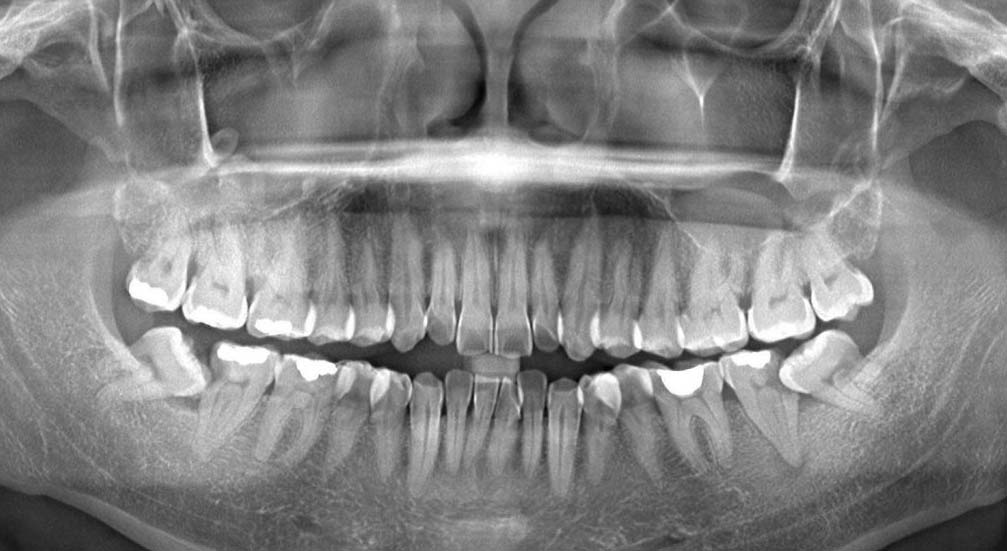

Bên cạnh đó, việc sắp xếp thời gian để đến nha khoa thăm khám, xử lý sớm chiếc răng khôn là điều cần thiết. Bạn cần chụp phim X-quang để biết được tình trạng răng của mình, từ đó bác sĩ tư vấn phương pháp nhổ và chi phí trước khi nhổ…

Chụp X-quang răng khôn bệnh nhân

Bước 2: Chụp x-quang để biết được tình trạng răng một cách chính xác nhất. Từ đó, đưa sẽ ra phương pháp điều trị phù hợp cho từng bệnh nhân